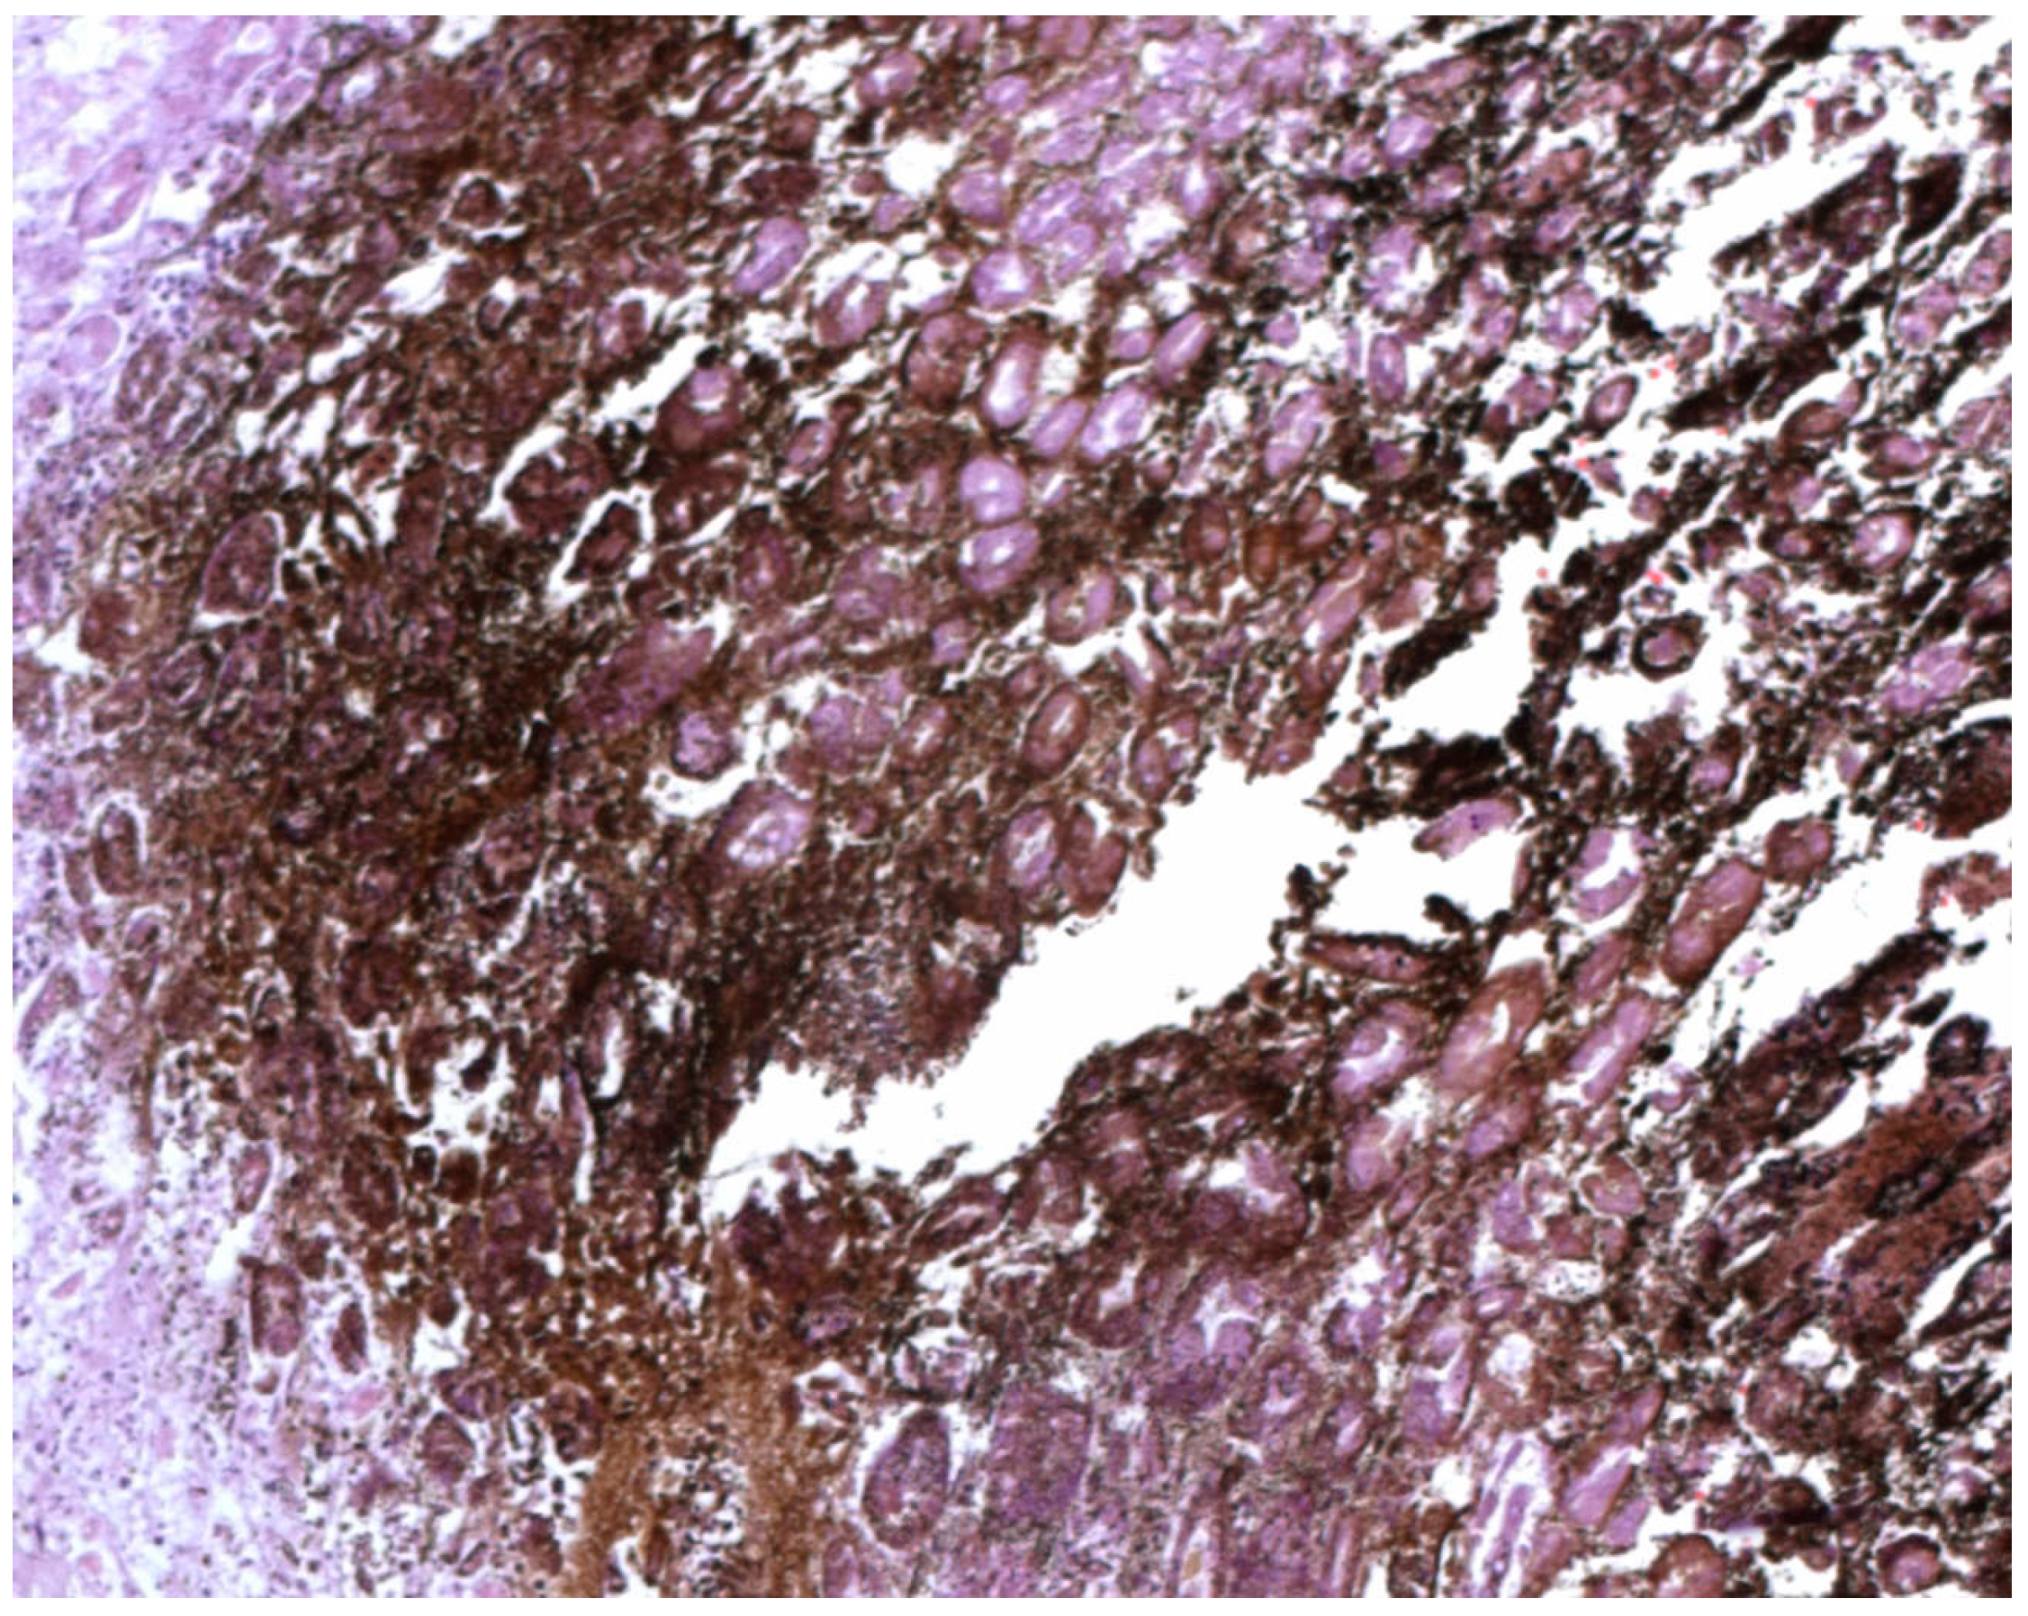

Biological Mechanisms behind Wischnewsky Spots Finding on Gastric Mucosa: Autopsy Cases and Literature Review

3.1.2. Case 2

3.3.2. Case 2